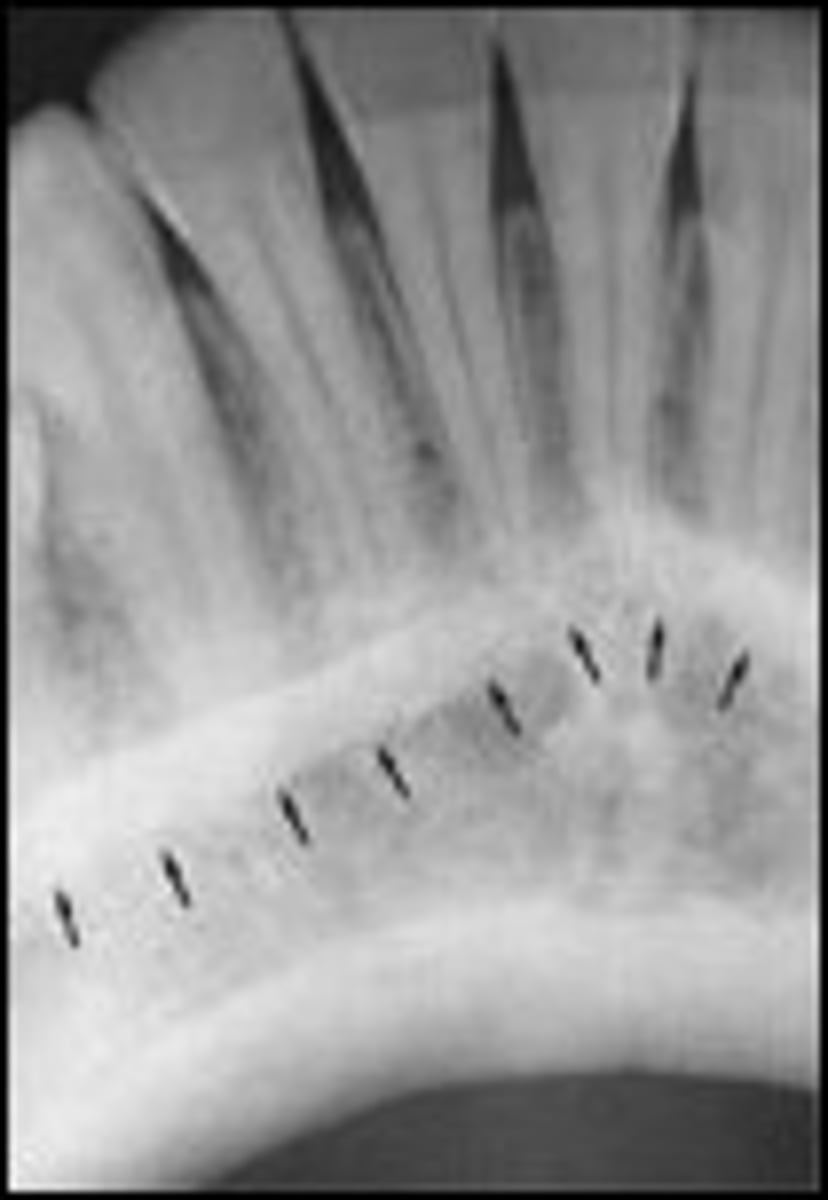

ID a mental ridge on radiograph